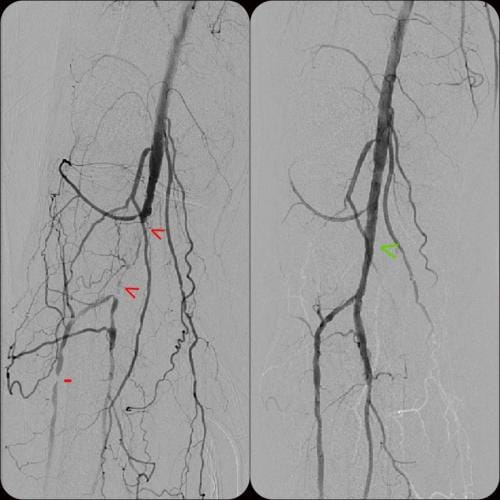

- What is the experience? Choose a specialist that has a proven record of tackling difficult cases successfully. Some specialist choose to only do the simple procedures and refer the rest to surgery. Additionally, if the specialist can only perform simple procedures they may have a higher rate of complication if the case turns out to be more difficult than expected. Our specialist has performed numerous successful complex procedures from the groin, knee and foot. See our prior cases here.

During these procedures: Sedation is given to help you relax. Next, a tiny tube is gently inserted in an artery, usually in the groin or upper thigh area. You will be given a local anesthetic to numb the area where the tube will be inserted. It is then guided through the blood vessel toward the disease artery. When it’s in place, a dye is injected through the catheter to visualize the arteries. An X-ray is taken to help the physician pinpoint the area that is blocked or narrowed. The physician then uses tiny wires and catheters to get through the diseased vessels. Depending on the images treatment may then be performed.

Angioplasty — a special catheter that has a balloon on one end is advanced into the diseased artery. This is temporarily inserted through the narrowed artery and inflated to flatten the plaque against the artery wall, opening the artery and restoring blood flow.

Stent placement —a stent is a small, expandable, leg pain angioplasty stent los Angeles san diegomesh-like tube that supports the artery and helps to keep it open. Implanting a stent does not require open surgery. The doctor inserts a catheter into an artery in your arm or leg, similar to the balloon angioplasty procedure. A specially designed catheter delivers the stent to the narrow area in the artery. The stent is expanded, flattening the plaque against the artery wall and holding the artery open with a mesh tube. The catheter used to deliver the stent is then removed, but the stent stays in your artery permanently to maintain healthy blood flow.

Atherectomy — a specialized catheter that modifies the plaque in the arteries. Unlike angioplasty and stenting, which are designed to move plaque to the sides, atherectomy involves cutting and removing or sanding down the plaque from the artery, restoring normal blood flow.

Superior catheter and wire skills is essential in a delicate procedure such as treating blocked arteries. We treat a number of patients that have had failures by other specialists. Our doctor is an image-guided specialist having performed over 5,000 procedures with successful experience in venous and arterial blockages. Having a wide array of experience in different image-guided procedures brings a unique skill set to ensure that you have the most successful outcome without complication. Rest assured that our specialist can not only complete simple procedures like other centers, but he has a consistent history of successfully treating complex cases.